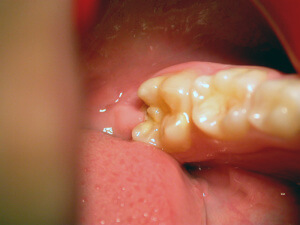

Caries is a disease. It is the most widespread disease in the world. The bacterial dental plaque (also called a biofilm) is the main cause of the infection of the teeth and the supportive tissues, i.e. of the caries and periodontal diseases respectively. The accumulation of dental plaque and the colonization of bacteria lead to the appearance of dental and periodontal pathology.

Microbes cling on various surfaces and form the biofilm. In addition, frequent intake of carbohydrates (especially sweets) gets metabolized to acids. The pH of dental plaque becomes acidic repeatedly, and that favors acid tolerant bacteria, such as streptococci and lactobacilli that are the most dangerous bacteria for caries.